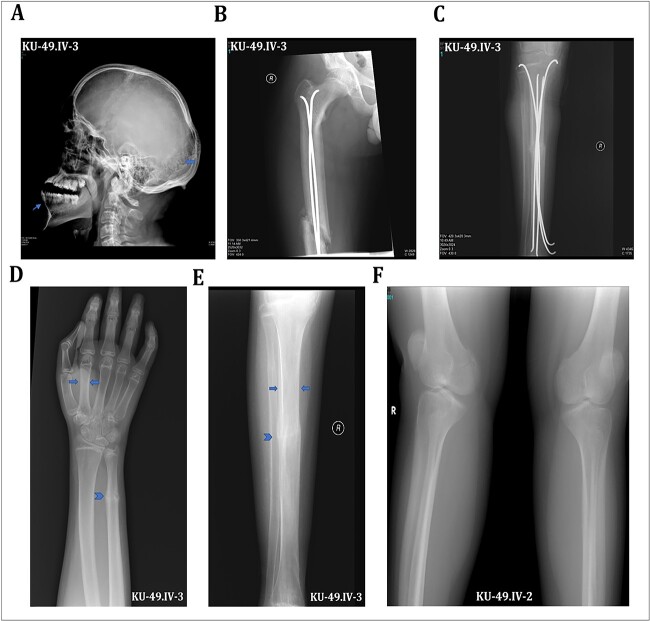

Osteogenesis imperfecta (OI) is a heterogeneous spectrum of hereditary genetic disorders that cause bone fragility, through various quantitative and qualitative defects of type 1 collagen, a triple helix composed of two α1 and one α2 chains encoded by COL1A1 and COL1A2, respectively. The main extra-skeletal manifestations of OI include blue sclerae, opalescent teeth, and hearing impairment. Moreover, multiple genes involved in osteoblast maturation and type 1 collagen biosynthesis are now known to cause recessive forms of OI. In this study a multiplex consanguineous family of two affected males with OI was recruited for genetic screening. To determine the causative, pathogenic variant(s), genomic DNA from two affected family members were analyzed using whole exome sequencing, autozygosity mapping, and then validated with Sanger sequencing. The analysis led to the mapping of a homozygous variant previously reported in SP7/OSX, a gene encoding for Osterix, a transcription factor that activates a repertoire of genes involved in osteoblast and osteocyte differentiation and function. The identified variant (c.946C > T; p.Arg316Cys) in exon 2 of SP7/OSX results in a pathogenic amino acid change in two affected male siblings and develops OI, dentinogenesis imperfecta, and craniofacial anomaly. On the basis of the findings of the present study, SP7/OSX:c. 946C > T is a rare homozygous variant causing OI with extra-skeletal features in inbred Arab populations.